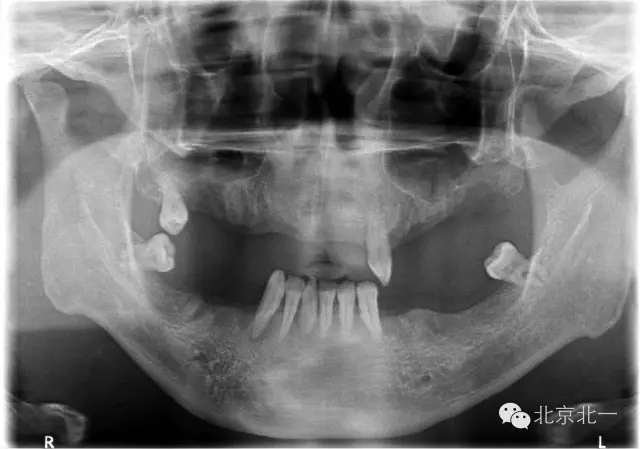

圖二:術(shù)前全景片

重度牙周炎患者一例 牙齒無法保留